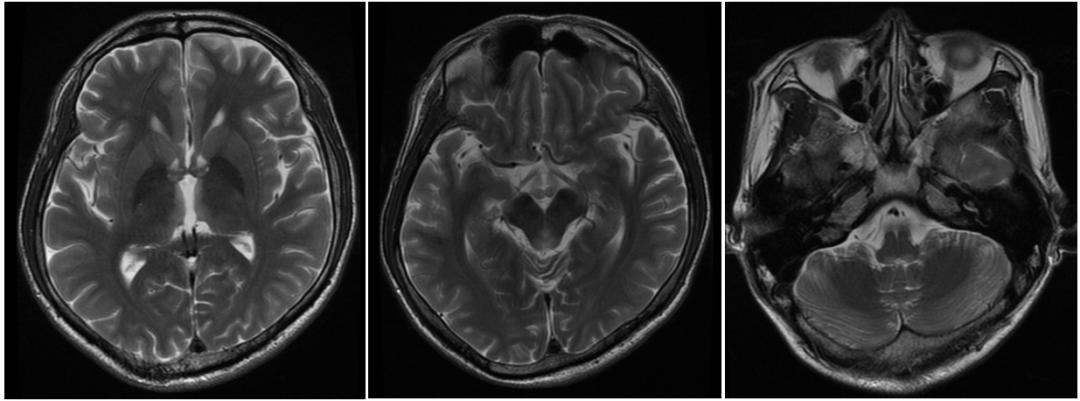

顱腦MRI示:雙側第三、第四腦室周、雙側丘腦內側、中腦導水管周圍、延髓背側對稱性片狀等T1、稍長T2信號,T2FLAIR呈高信號,DWI呈稍高信號。